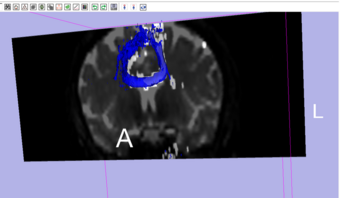

Stochastic Tractography on Phantom

To address the uncertainty of deterministic tractography methods, stochastic tractography methods have been developed to quantify the uncertainty associated with estimated fibers (Bjornemo et al., 2002). Method uses a propagation model based on stochastics and regularization, which allows paths originating at one point to branch and return a probability distribution of possible paths. One can generate thousands of fibers starting in the same point by sequentially drawing random step directions. This gives a very rich model of the fiber distribution, as contrasted with single fibers produced by conventional tractography methods. Moreover, from a large number of sampled paths, probability maps can be generated, providing better estimates of connectivity between several anatomical locations.

This tutorial will walk users through the multiple stages of the python stochastic tractography module, where the inputs are a DWI and a region of interest labelmap. This will include:

1. Loading the Volumes

2. Extracting DWI and getting Baseline DWI threshold levels

3. Using the many features of the Python Stochastic Tractography module, including smoothing, otsu-like and white matter mask generation, and other settings.

4. Generating a Connectivity Map, which is able to be thresholded and customized.